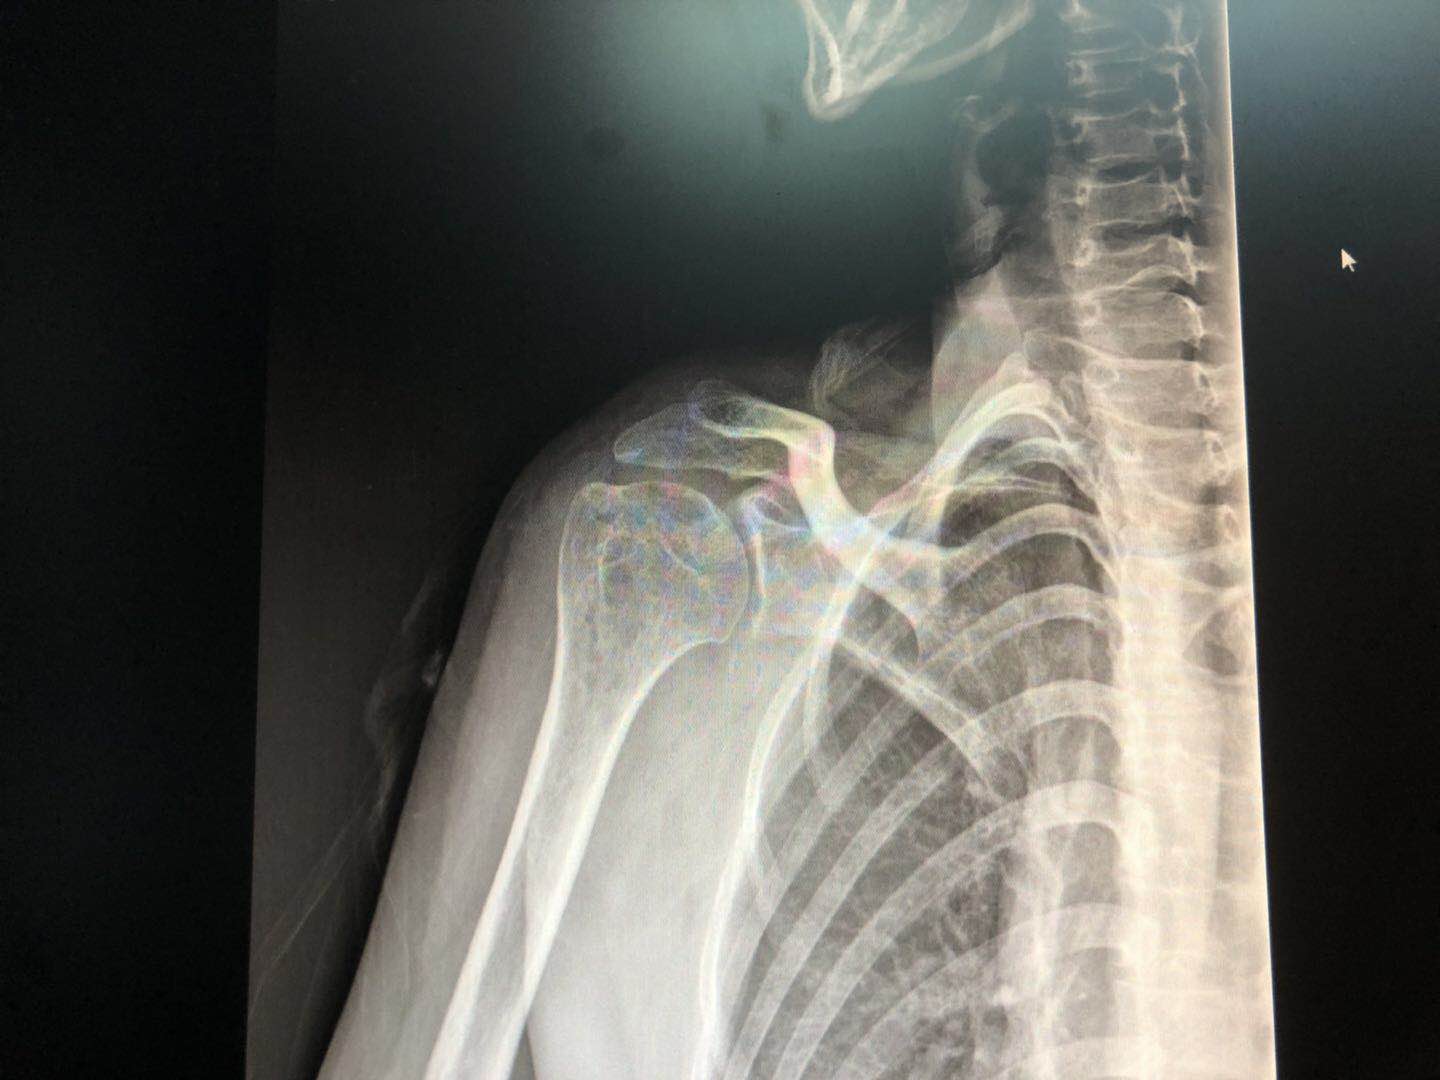

到医院后拍了个X光片(如下图)提示肩关节周围炎症,也就是老百姓口中常说的“肩周炎”